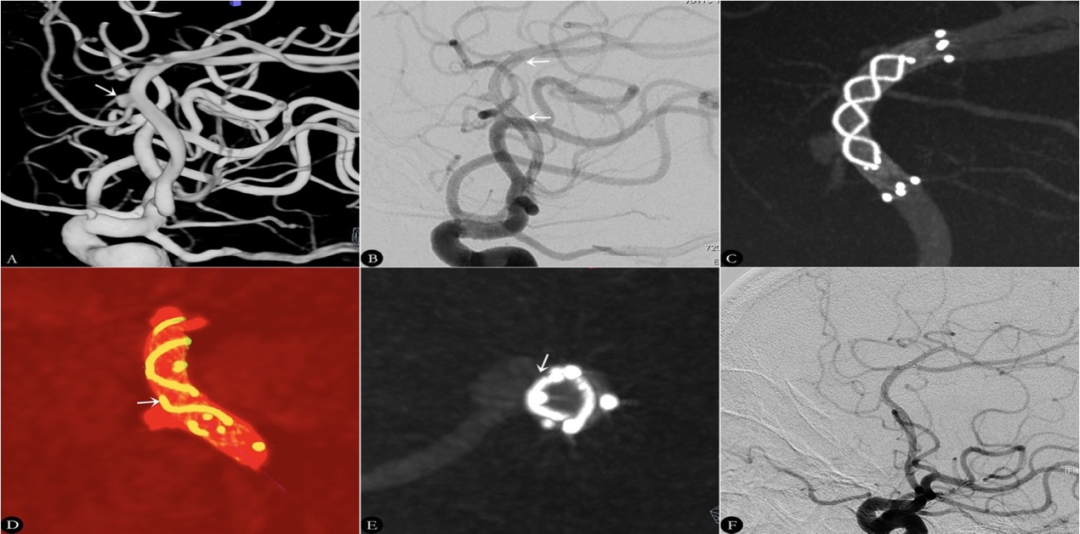

图3.右侧大脑前动脉瘤支架植入术及贴壁优化前后影像

A、B、C.2D-DSA和提示右侧大脑前动脉A2段动脉瘤,大小5.2×6.8mm,瘤颈5mm,头颈比1.36,载瘤动脉远端和近端直径分别为2.1mm和2.9mm(白色箭头示动脉瘤)。D.术后影像学显示动脉瘤即刻对比剂明显滞留(白色箭头示动脉瘤,黑色箭头显示支架的头部和尾部)。E、G.HR-FDCT显示支架完全释放但部分区域贴壁不良(白色箭头示载瘤动脉区域贴壁不良,黑色箭头示瘤颈区域贴壁不良;其中绿色部分为支架及其编制丝,红色部分为载瘤动脉和动脉瘤);F、H.经J形导丝和球囊促进贴壁后HR-FDCT显示支架贴壁良好(白色箭头示载瘤动脉区域现贴壁良好,黑色箭头示瘤颈区域现贴壁)。